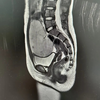

8岁女孩发育来月经,检查发现“作怪”元凶:卵巢长出柚子大肿瘤